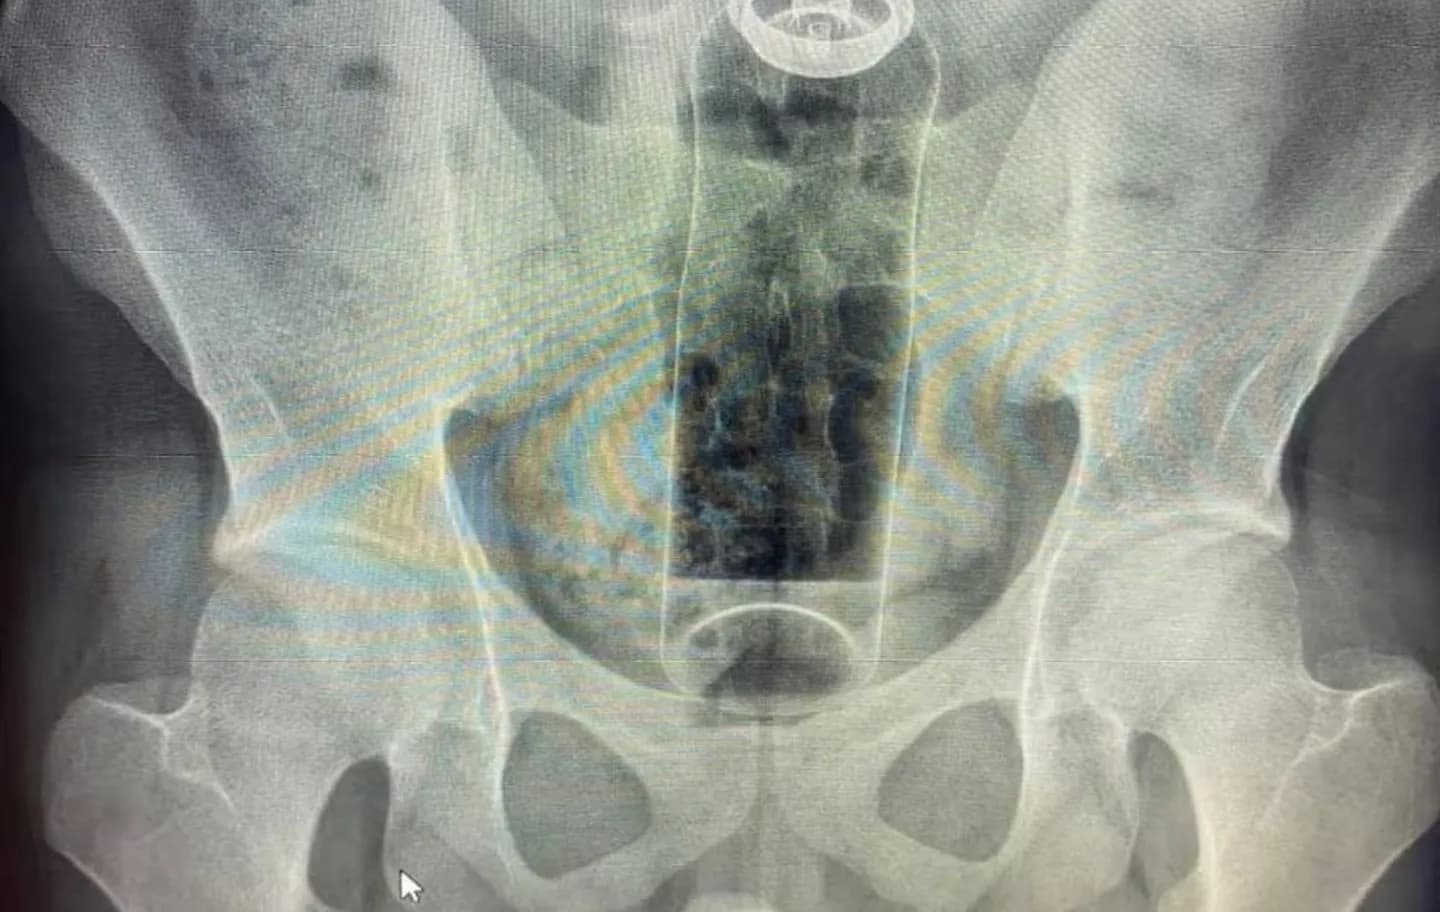

Mala com R$ 1,7 milhão é interceptada a caminho de Brasília

A Polícia Federal (PF) formalizou a apreensão, nesta quinta-feira (29/1), de aproximadamente R$ 1,7 milhão em espécie. O dinheiro foi encontrado em um veículo pelo Comando de Operações de Divisas (COD) da Polícia Militar de Goiás (PMGO), na BR-050, no município de Cristalina (GO). Dois homens estavam no automóvel. Durante a fiscalização, os ocupantes não conseguiram comprovar nem explicar a origem lícita do dinheiro. Levantamentos preliminares indicam que os envolvidos não possuem capacidade econômica compatível com a quantia apreendida, havendo indícios de que estariam atuando como “laranjas”. Diante da repercussão interestadual dos fatos e da suspeita de origem ilícita dos valores, a ocorrência foi apresentada à Superintendência Regional da Polícia Federal no Distrito Federal (SR/PF/DF). As investigações seguem para identificar a origem e a destinação dos recursos, não sendo descartada a possibilidade de utilização para o pagamento de vantagens indevidas. Reprodução: Metrópoles